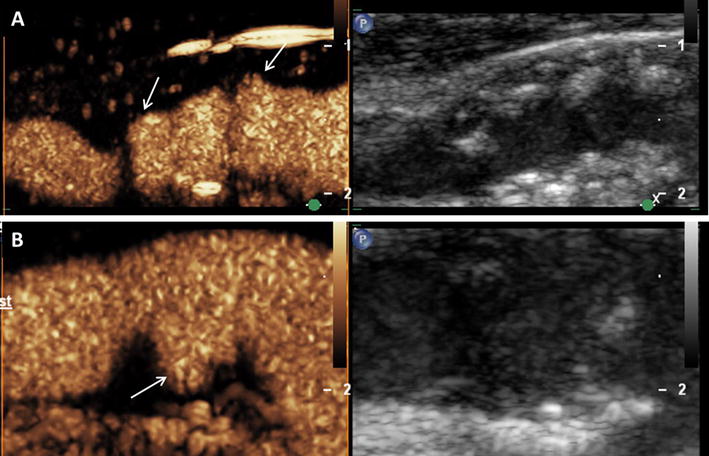

Assessment of vessel wall irregularities and plaque ulcerations on carotid artery using CEUS. a Mixed hypo- and hyperechoic plaques at the carotid bulb on B-mode ultrasound (right side) and CEUS imaging (left side) with surface irregularities (arrows). b Plaque ulceration (arrow) on CEUS imaging (left side) at the origin of the internal carotid artery not detected on B-mode ultrasound (right side)